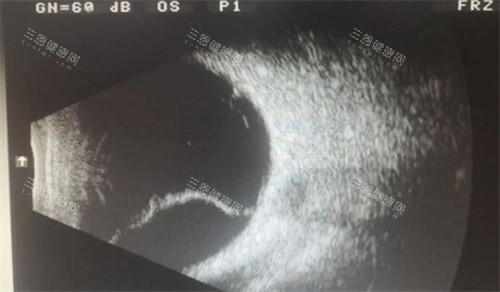

医生们能够运用靠前的检查设备,如OCT、眼底荧光血管造影等,比较准地诊断眼底病的病情。